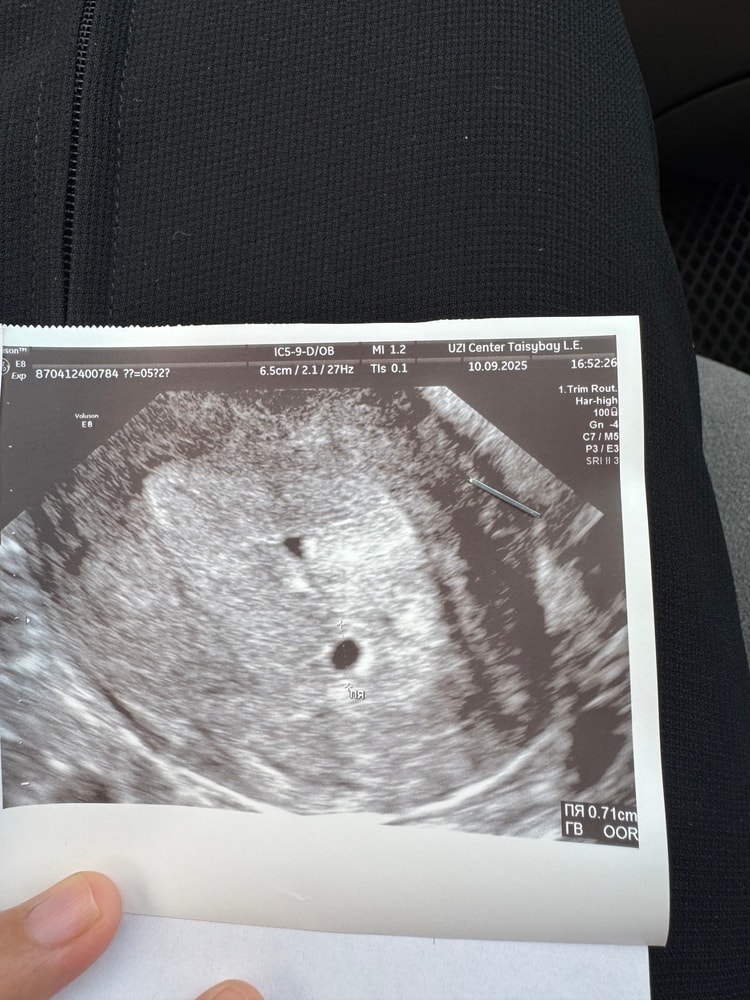

УЗИ, КТГ, доплерДобрый день! У кого было такое на первом узи сказали что двойня, через 3 дня сделала узи так как были боли низ живота там мне сказали что одно ПЯ?

2 узи разница узи 3 дня